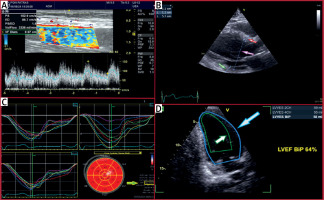

Figure 4

An asymptomatic patient with a well-tolerated high-flow AVF (transposed basilic vein). A – A flow volume > 3 l/min was measured at the brachial artery. B – Echocardiography depicted mild dilated and hypertrophied LV due to volume overload (green arrow: myocardial wall thickness, red arrow: myocardial septal thickness, purple arrow: LV diameter) with systolic indices (LV ejection fraction and global longitudinal strain) in the upper normal range. C – Global longitudinal strain: –19% (green-yellow arrow). D – LVEF: 64% (gray-blue arrow: LV diastole, white-green arrow: LV systole)